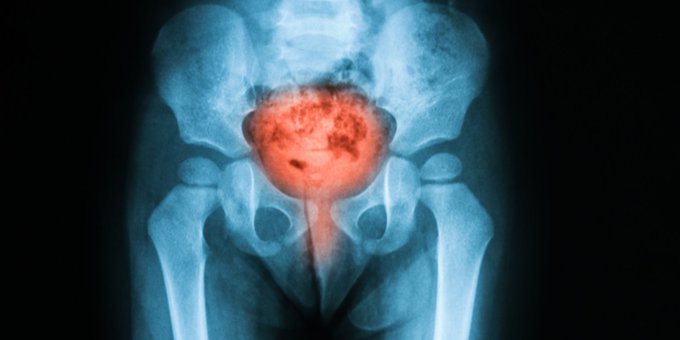

La incontinencia urinaria ocurre cuando no se puede impedir que la orina se escape de la uretra. ¿Cuáles son las causas de la incontinencia urinaria y cómo se trata? Eso y más aquí ow.ly/NiIw50yvdty